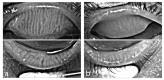

Despite decades of experience with hematopoietic stem cell transplantation, we are still faced with the delicate equipoise of achieving stable ocular health post-transplantation. This is because ocular graft-versus-host disease (oGvHD) following hematopoietic stem cell transplantation frequently occurs (≥50%) among transplant patients. To date, our understanding of the pathophysiology of oGvHD especially the involvement of the meibomian gland is still limited as a result of a lack of suitable preclinical models among other. Herein, the current state of the etiology and, pathophysiology of oGvHD based on existing pre-clinical models are reviewed. The need for additional pre-clinical models and knowledge about the involvement of the meibomian glands in oGvHD are emphasized.